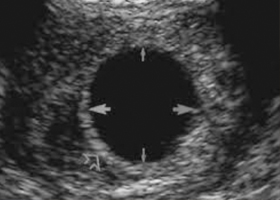

На основе ультразвукового исследования можно определить различные виды замершей беременности:

- Анэмбриония (отсутствие эмбриона в плодном яйце).

Для ясности, отметим, что эмбрион считается таковым до конца седьмой недели, а с восьмой недели он уже классифицируется как плод. Анэмбриония может проявляться в двух формах: первая — когда эмбрион не образовался изначально, вторая — когда его развитие остановилось на очень ранних этапах (до пятой недели).

Если при УЗИ у женщины обнаруживается плодное яйцо без эмбриона, это может указывать как на ранний срок беременности, так и на анэмбрионию. В любом случае, УЗИ повторяют через неделю для наблюдения за динамикой.

Гибель плода рассматривается в тех случаях, когда он сначала развивался нормально, а затем остановил свое развитие. Если гибель произошла за несколько дней до УЗИ, плодное яйцо и плод могут выглядеть нормально по форме и размерам, но признаки жизни отсутствуют (движения, которые начинаются с восьмой недели, и сердцебиение, которое можно зафиксировать на УЗИ с пятой-шестой недели).

При длительном нахождении замершего плода в матке его невозможно рассмотреть на УЗИ, так как плодное яйцо претерпевает значительные изменения (деформация, нечеткие контуры, множественные перетяжки). Размеры матки при этом отстают от предполагаемого срока, и отсутствуют признаки жизнедеятельности плода.

Можно утверждать, что в постановке данного диагноза, особенно на ранних сроках, ключевую роль играет ультразвуковое исследование. Благодаря его возможностям можно выявить замершую беременность до появления каких-либо симптомов. УЗИ может проводиться через брюшную стенку или через влагалище (трансвагинальное УЗИ).

Последний метод более точен, так как опытный специалист может увидеть плодное яйцо уже на четвертой неделе при размерах 2-3 мм! Более информативным считается трансвагинальное УЗИ с пятой недели беременности. Желточный мешок с помощью этого метода обнаруживается раньше, чем эмбрион.

Согласно Клиническим рекомендациям 2016 года, замершая беременность диагностируется при отсутствии сердцебиения при копчико-теменном размере эмбриона более 7 мм и отсутствии структуры эмбриона при диаметре плодного яйца более 25 мм. Отсутствие сердцебиения на ранних сроках и при меньших размерах эмбриона не является основанием для постановки этого диагноза. Существуют и другие критерии, позволяющие выявить замершую беременность:

- у эмбриона нет сердцебиения через 2 недели после выявления плодного яйца без желточного мешка;

- отсутствие сердцебиения через 11 дней после выявления плодного яйца с желточным мешком.

Сравнение клинических данных, таких как размеры матки и срок беременности по календарю, с результатами ультразвукового исследования (УЗИ) позволяет установить диагноз и уточнить срок нахождения плодного яйца в матке. В первом триместре наиболее эффективным методом диагностики считается трансвагинальное УЗИ. В соответствии с медицинскими рекомендациями, УЗИ должно проводиться в период с 11 по 14 недели, когда завершается эмбриогенез. В более ранние сроки исследование осуществляется только по медицинским показаниям. Во время обследования могут быть выявлены: отсутствие сердцебиения эмбриона (которое начинает фиксироваться с 5 недели), а также истончение и неоднородность хориона.